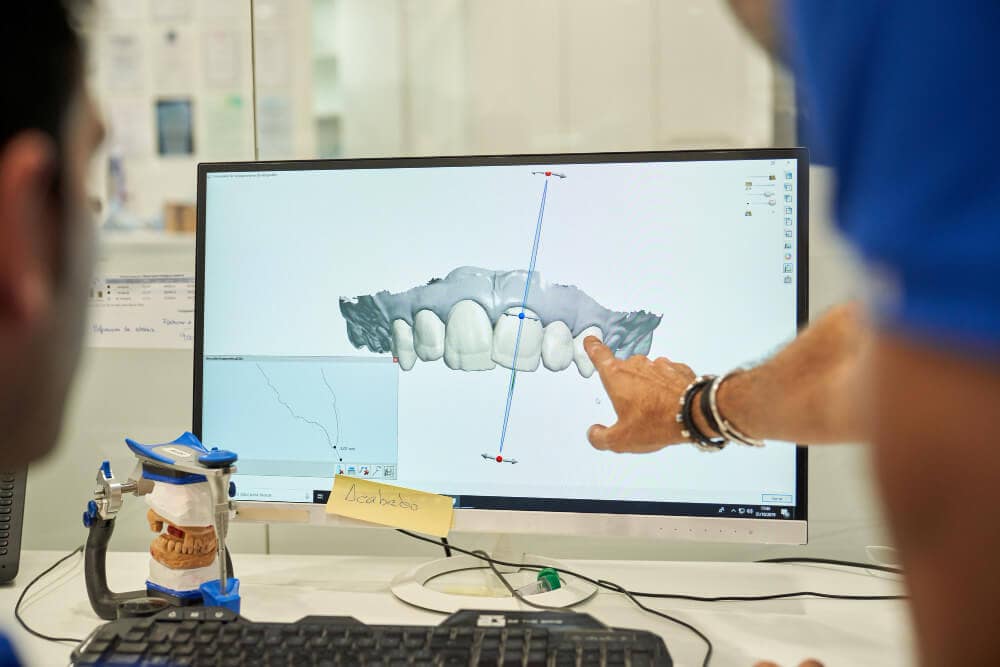

Impresión 3D en Implantología: La Era de la Precisión Personalizada

BlogImpresión 3D en Implantología: La Era de...

Leer másCirugía Guiada por Computadora: La Implantología del Futuro, Hoy

BlogCirugía Guiada por Computadora: La Implantología del...